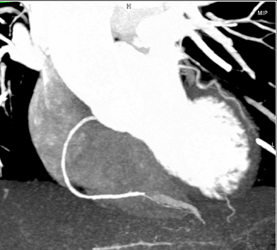

Diagnosis

Normal LAD